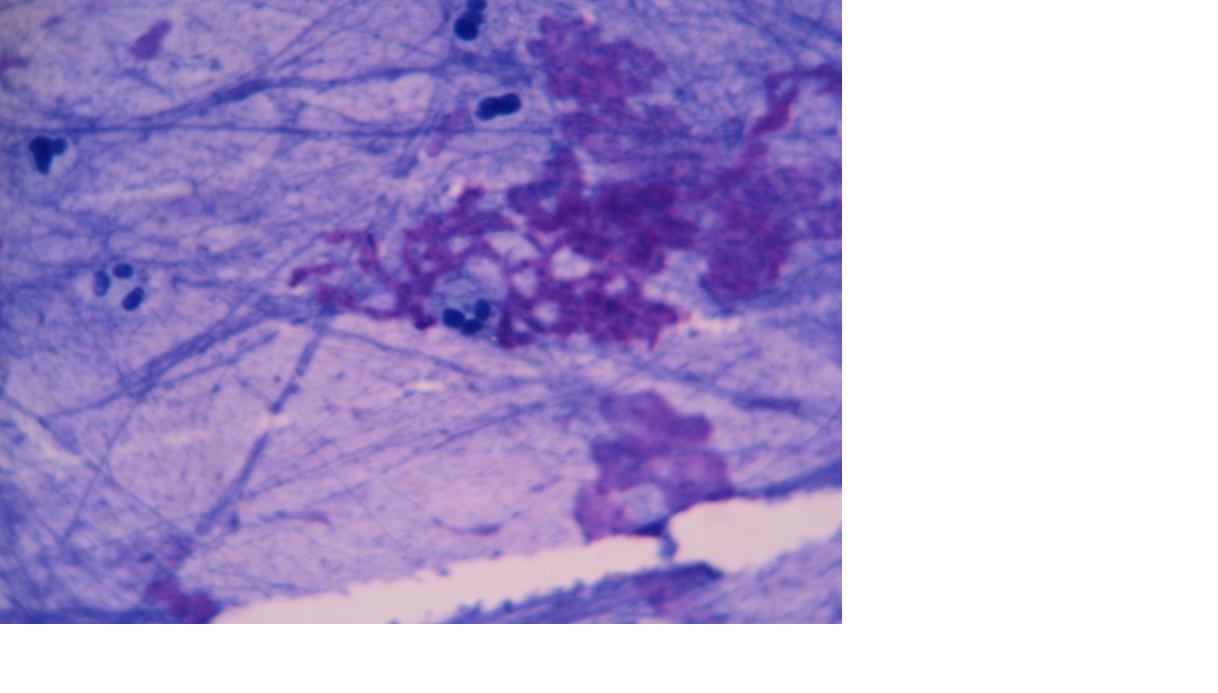

卡氏肺孢子虫染为黑色,背景绿色或蓝绿色。